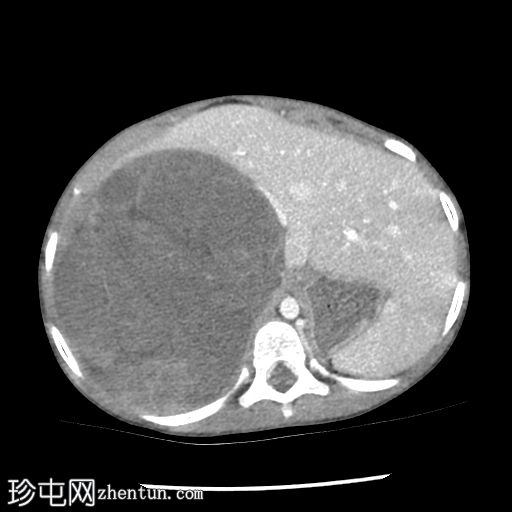

轴位

右肾向下移位至中线,呈水平位。肾上极可见一大小不一、边界相对清晰的肿块。未见明显钙化或坏死。肿块延伸至中线,但未越过主动脉/中线左侧。下腔静脉上段向前左侧移位。尽管移位,右肾静脉和动脉外观正常,未见狭窄/扩张或明显的肾静脉血栓形成。

结肠和小肠袢,尤其是在右侧腹部,向下移位,但外观无明显异常。

未见腹膜后淋巴结肿大。骨骼结构外观正常,无明显的溶骨性或成骨性改变。